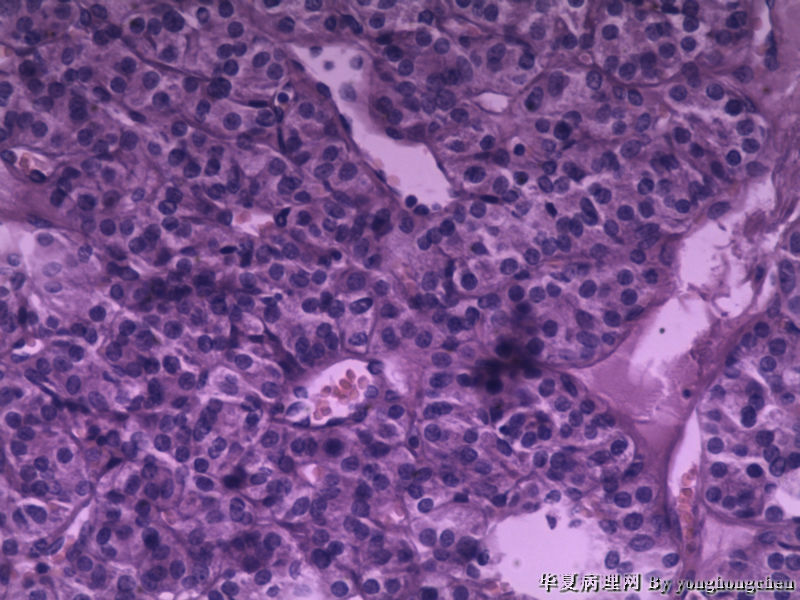

可不可能是嗜酸细胞腺瘤?

• 可不可能是嗜酸细胞腺瘤?图2

图2

女,22岁,左侧甲状腺肿物6*4*2厘米,包膜完整,切面灰红,质软。

图二间质内似有玻璃样物质,染PAS,排除HTT。

注意观察包膜侵犯情况。

我看还像有甲状旁腺组织?